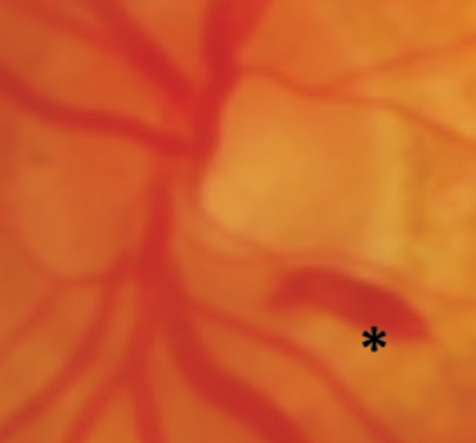

A subhyaloid hemorrhage is recognized by the presence of blood that is extravasated beneath the retinal layer. They are commonly caused by acute trauma, although they are best known as a sign of SAH (Subarachnoid hemorrhage). Hemorrhages in SAH manifest as a “puff” of blood coming from the central disc.

Subhyaloid hemorrhages in the macula lead to a rapid and dramatic loss of vision. Photoreceptor toxicity can develop when the retina is exposed to hemoglobin and its catabolites for an extended period.